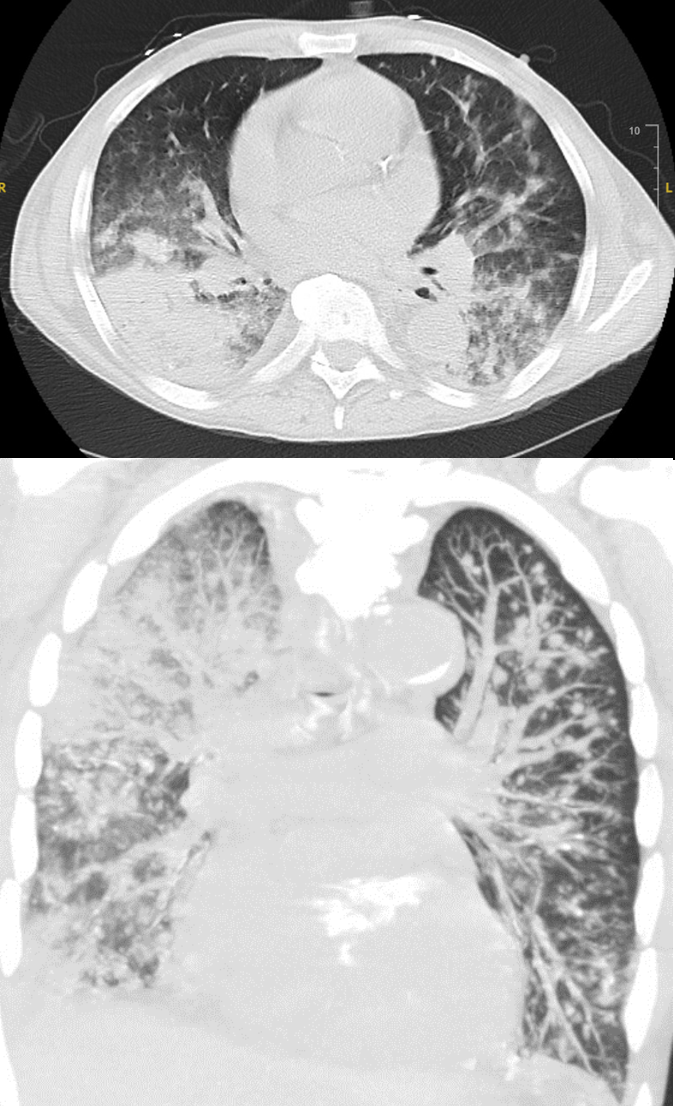

The patient underwent percutaneous liver biopsy for incidental numerous small ring enhancing lesions which was complicated by hemorrhagic shock requiring hospitalization and resuscitation with blood products and arterial embolization. One week later, patient developed acute respiratory failure. A chest computed tomography (CT) scan showed bilateral pulmonary opacities and diffuse bilateral small lung nodules. The patient’s respiratory status deteriorated despite broad-spectrum antibiotics. Bronchoscopy showed a mobile clot resulting in obstruction of the right mainstem and complete atelectasis of the right lung, the clot was removed. Postoperatively, patient had hemoptysis and respiratory failure requiring intubation. Repeat chest CT scan showed progressive pulmonary lesions and diffuse alveolar hemorrhage

Given immunosuppressed state, opportunistic infections were considered, serum HHV-8 was positive at 4400 copies/mL. Imaging of the body showed multiple enlarged lymph nodes (LN). An excisional biopsy of the right inguinal LN revealed a spindle cell neoplasm consistent with KS. Repeat bronchoscopy revealed multiple purple-red endobronchial lesions consistent with pulmonary KS. Diagnosis of advanced KS with pulmonary andLN involvement and probable liver involvement was made. Stage T1I0S1 according to the AIDS Clinical Trial Group staging system. Tacrolimus was switched to sirolimus and a dose of liposomal doxorubicin was given, however the patient’s clinical status worsened, and he expired.